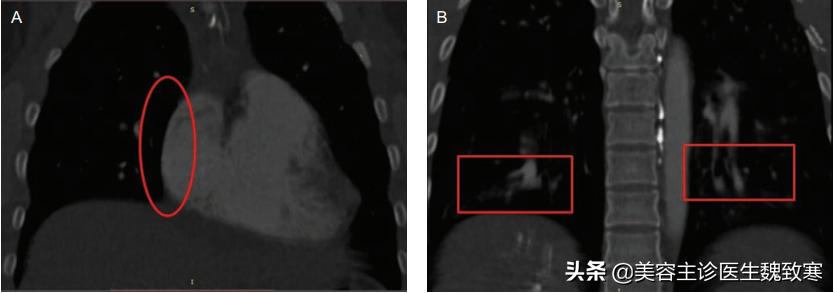

图2A、图2B

肺CT血管造影和三维重建显示右下叶后基底段肺动脉分支持续中断(图3)。经胸超声心动图显示心功能基本正常,无瓣膜异常。